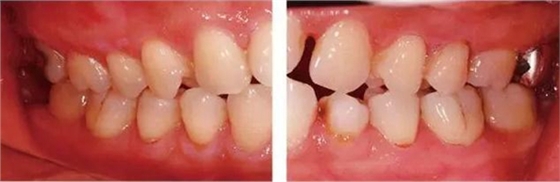

●參考病例② 25歲女性

25歲女性。菌斑控制狀態(tài)不好。齦溝除磨牙處外全在3mm以下,X光照片上左上、右下、左下的第一磨牙上有垂直性骨吸收。這個(gè)病例是參考病例①10年前的狀態(tài),是典型的侵襲性牙周炎局部型。